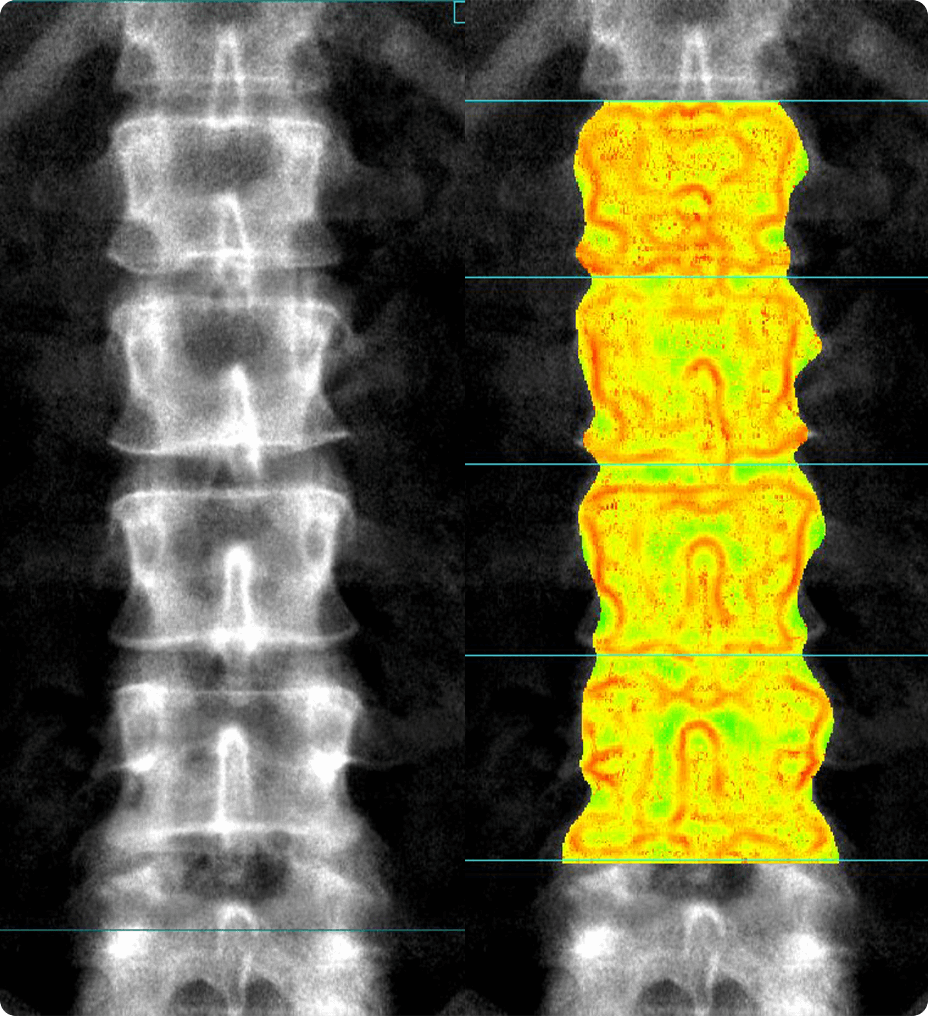

Comprehensive stenosis measurement and plaque analysis of any vasculature

• Perform vessel analysis from any 3D or reformatted image with one or two clicks.